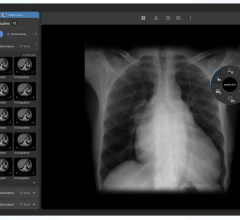

The NovaMG breast imaging viewer combines the tool set of NovaPACS with customizable mammographic reading and hanging protocol sequences. FDA 510(k) cleared and IHE compliant, it supports multi-modality viewing and iCad and R2 structured reports.

The viewer enables direct receipt of digital mammographic images from the modality while pre-fetching from the PACS archive is initiated via DICOM modality worklist.

Offered as an option to NovaRad’s existing radiologist view stations, the viewer provides all pixels viewing that allows for searching of all image pixels and incorporates Tabár’s systematic viewing masks to enhance perception of subtle radiographic abnormalities. All annotations and additions to image information such as Grayscale Softcopy Presentation State (GSPS), queried and retrieved images and structured reports are stored in the PACS upon completion of interpretation.